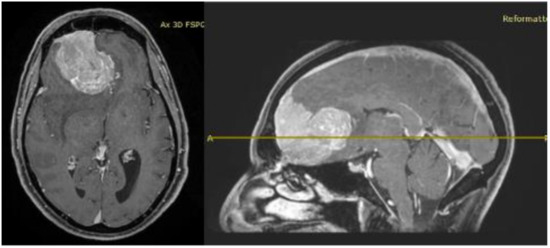

2. Case Report